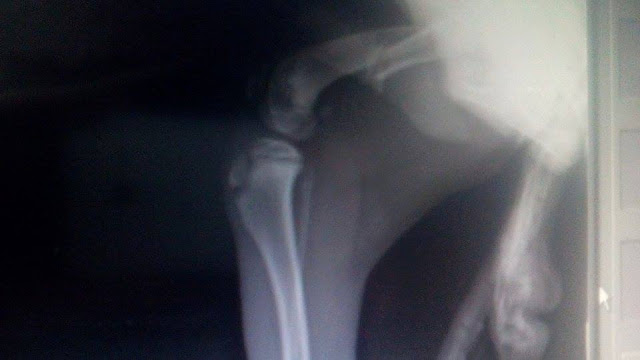

1 καταγμα η Κλειω και 3 ο Buter στα ποδια

Η Κλειω έχει συντριπτικό κάταγμα μηριαιου με παρεκτοπηση.

Θα πρεπει να γίνει χειρουργική αναταξη με πλάκα.

Ο Butter έχει συντριπτικό κάταγμα μηριαιου με παρεκτοπηση και αμφοτεροπλευρο κάταγμα κνημης περονης. Ιδια διαδικασία αναταξης.

Ειναι στην ουσια 4 χειρουργεια και το κόστος είναι 800 ευρώ.